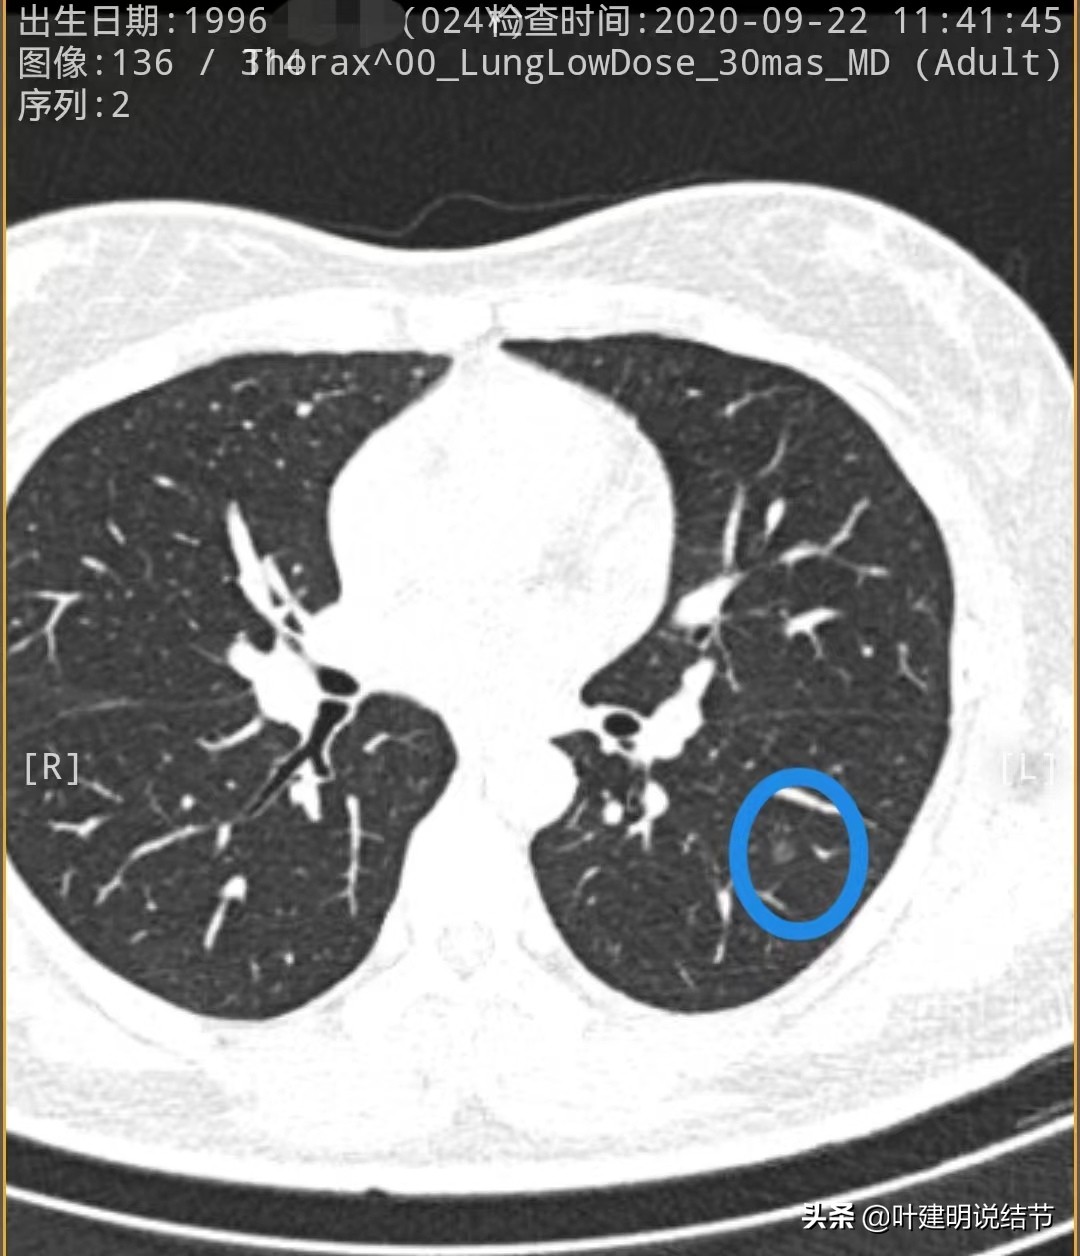

先来看2020年时的CT图像:

左下叶淡磨玻璃结节,轮廓较清,没有实性成分,以不典型增生可能性为大些

左下叶另一结节,密度低,轮廓 也清,考虑腺体胶驱病变,不典型增生或原位癌可能性大些